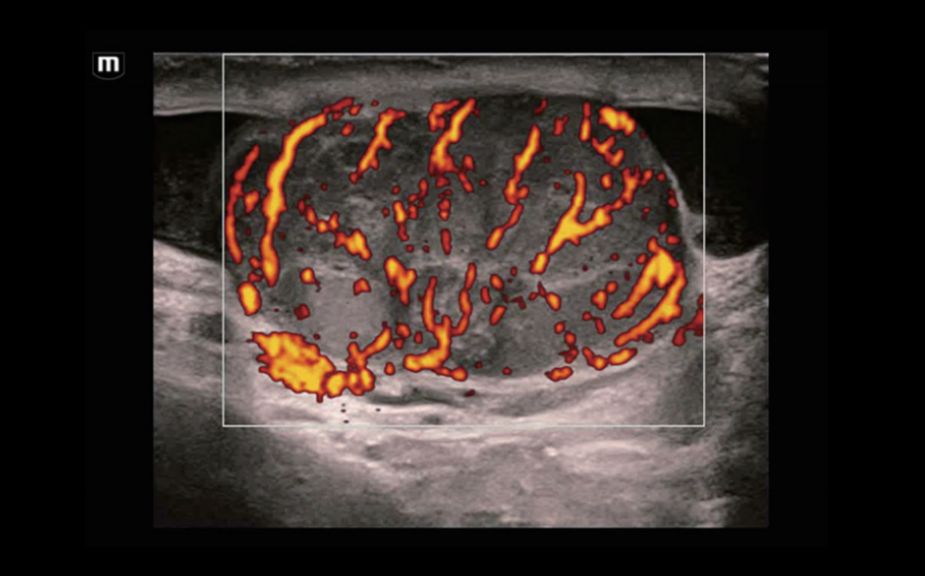

–Ě–ĺ–≤–Ķ–Ļ—ą–ł–Ļ –Ņ–ĺ–ī—Ö–ĺ–ī –ļ –ł–∑—É—á–Ķ–Ĺ–ł—é —Ā–ĺ—Ā—É–ī–ł—Ā—ā–ĺ–Ļ –≥–Ķ–ľ–ĺ–ī–ł–Ĺ–į–ľ–ł–ļ–ł: V Flow

–ė—Ā–Ņ–ĺ–Ľ—Ć–∑—É—é—ā—Ā—Ź –ľ–į—Ä–ļ–ł—Ä–ĺ–≤–į–Ĺ–Ĺ—č–Ķ —Ü–≤–Ķ—ā–ĺ–ľ –≤–Ķ–ļ—ā–ĺ—Ä–į –ī–Ľ—Ź –ł–Ĺ–ī–ł–ļ–į—Ü–ł–ł –∑–Ĺ–į—á–Ķ–Ĺ–ł—Ź —Ā–ļ–ĺ—Ä–ĺ—Ā—ā–ł –ł –Ĺ–į–Ņ—Ä–į–≤–Ľ–Ķ–Ĺ–ł—Ź –ī–≤–ł–∂–Ķ–Ĺ–ł—Ź –ļ–Ľ–Ķ—ā–ĺ–ļ –ļ—Ä–ĺ–≤–ł. –Ď–Ľ–į–≥–ĺ–ī–į—Ä—Ź —Ā–≤–Ķ—Ä—Ö–≤—č—Ā–ĺ–ļ–ĺ–Ļ —á–į—Ā—ā–ĺ—ā–Ķ –ļ–į–ī—Ä–ĺ–≤ V Flow –ĺ–Ī–Ķ—Ā–Ņ–Ķ—á–ł–≤–į–Ķ—ā —á—Ä–Ķ–∑–≤—č—á–į–Ļ–Ĺ–ĺ —á–Ķ—ā–ļ—É—é, —ā–ĺ—á–Ĺ—É—é –ł –Ĺ–Ķ–∑–į–≤–ł—Ā–ł–ľ—É—é –ĺ—ā —É–≥–Ľ–į –ļ–ĺ–ľ–Ņ–Ľ–Ķ–ļ—Ā–Ĺ—É—é –ĺ—Ü–Ķ–Ĺ–ļ—É —Ā–ĺ—Ā—É–ī–ł—Ā—ā–ĺ–Ļ –≥–Ķ–ľ–ĺ–ī–ł–Ĺ–į–ľ–ł–ļ–ł —Ā –≤–ĺ–∑–ľ–ĺ–∂–Ĺ–ĺ—Ā—ā—Ć—é –≤—Ā–Ķ—Ā—ā–ĺ—Ä–ĺ–Ĺ–Ĺ–Ķ–≥–ĺ –į–Ĺ–į–Ľ–ł–∑–į.

V Flow

–Ě–ĺ–≤–Ķ–Ļ—ą–ł–Ļ –Ņ–ĺ–ī—Ö–ĺ–ī –ļ –ł–∑—É—á–Ķ–Ĺ–ł—é —Ā–ĺ—Ā—É–ī–ł—Ā—ā–ĺ–Ļ –≥–Ķ–ľ–ĺ–ī–ł–Ĺ–į–ľ–ł–ļ–ł: V Flow

–ė—Ā–Ņ–ĺ–Ľ—Ć–∑—É—é—ā—Ā—Ź –ľ–į—Ä–ļ–ł—Ä–ĺ–≤–į–Ĺ–Ĺ—č–Ķ —Ü–≤–Ķ—ā–ĺ–ľ –≤–Ķ–ļ—ā–ĺ—Ä–į –ī–Ľ—Ź –ł–Ĺ–ī–ł–ļ–į—Ü–ł–ł –∑–Ĺ–į—á–Ķ–Ĺ–ł—Ź —Ā–ļ–ĺ—Ä–ĺ—Ā—ā–ł –ł –Ĺ–į–Ņ—Ä–į–≤–Ľ–Ķ–Ĺ–ł—Ź –ī–≤–ł–∂–Ķ–Ĺ–ł—Ź –ļ–Ľ–Ķ—ā–ĺ–ļ –ļ—Ä–ĺ–≤–ł. –Ď–Ľ–į–≥–ĺ–ī–į—Ä—Ź —Ā–≤–Ķ—Ä—Ö–≤—č—Ā–ĺ–ļ–ĺ–Ļ —á–į—Ā—ā–ĺ—ā–Ķ –ļ–į–ī—Ä–ĺ–≤ V Flow –ĺ–Ī–Ķ—Ā–Ņ–Ķ—á–ł–≤–į–Ķ—ā —á—Ä–Ķ–∑–≤—č—á–į–Ļ–Ĺ–ĺ —á–Ķ—ā–ļ—É—é, —ā–ĺ—á–Ĺ—É—é –ł –Ĺ–Ķ–∑–į–≤–ł—Ā–ł–ľ—É—é –ĺ—ā —É–≥–Ľ–į –ļ–ĺ–ľ–Ņ–Ľ–Ķ–ļ—Ā–Ĺ—É—é –ĺ—Ü–Ķ–Ĺ–ļ—É —Ā–ĺ—Ā—É–ī–ł—Ā—ā–ĺ–Ļ –≥–Ķ–ľ–ĺ–ī–ł–Ĺ–į–ľ–ł–ļ–ł —Ā –≤–ĺ–∑–ľ–ĺ–∂–Ĺ–ĺ—Ā—ā—Ć—é –≤—Ā–Ķ—Ā—ā–ĺ—Ä–ĺ–Ĺ–Ĺ–Ķ–≥–ĺ –į–Ĺ–į–Ľ–ł–∑–į.

V Flow